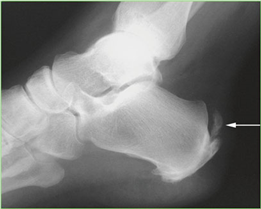

Conversely, hallux rigidus represents a degenerative cascade characterized by osteophyte formation, dorsal impingement, and progressive loss of sagittal plane motion at the first MTP joint. While trauma and inflammatory arthropathies can precipitate this condition, the most common etiology is idiopathic, often linked to an elevated or elongated first metatarsal (metatarsus primus elevatus), which alters the joint's instant center of rotation and accelerates articular wear. Recognizing these distinct pathophysiological pathways is paramount for the orthopedic surgeon, as it dictates the selection of joint-sparing osteotomies versus joint-sacrificing arthrodesis.

Weight-bearing anteroposterior (AP), lateral, and sesamoid axial radiographs are mandatory. On the AP view, the surgeon measures the Hallux Valgus Angle (HVA, normal < 15°), the Intermetatarsal Angle (IMA, normal < 9°), and the Distal Metatarsal Articular Angle (DMAA). The lateral view is scrutinized for Meary's angle (talo-first metatarsal angle) to identify midfoot collapse, as well as the presence of dorsal osteophytes indicative of hallux rigidus. The sesamoid axial view is critical for assessing the degree of sesamoid subluxation and the integrity of the crista.

Avascular necrosis of the metatarsal head is a devastating complication primarily associated with distal osteotomies. It presents with insidious onset of pain, swelling, and eventual radiographic collapse of the articular surface. Prevention is paramount and relies on preserving the plantar-lateral soft tissue attachments during the lateral release. If symptomatic AVN occurs and progresses to joint destruction, the definitive salvage procedure is a first MTP arthrodesis, often requiring structural bone grafting to restore metatarsal length.